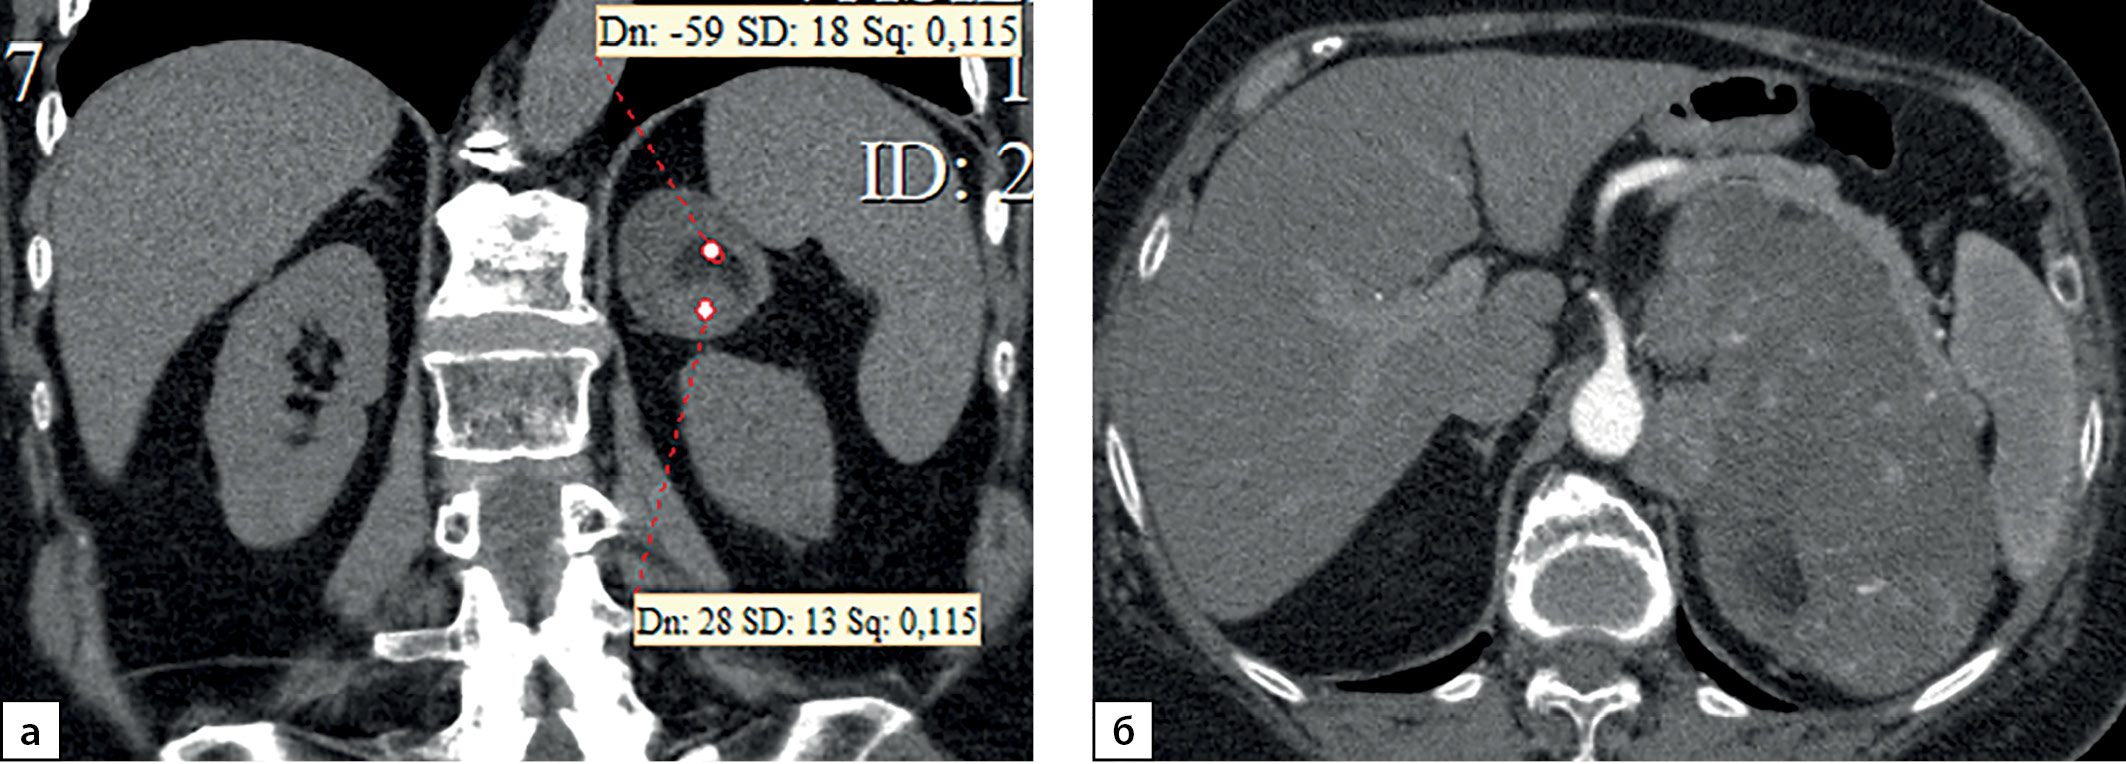

Размер опухолей в группе больных с первично выявленным АКР составлял 7,05 (5,85–7,67) см при минимальном значении 3 и максимальном — 23 см. Данные о размерах новообразований представлены на рис. 1. Злокачественные адренокортикальные опухоли мы условно разделили в зависимости от размера на маленькие до 4 см (6 случ.), средние от 4 до 6 см (11 случаев), большие от 6 до 10 (41 случай) и гигантские (рис. 2) — более 10 см (12 случай). Следует заметить, что от размеров опухоли зависит выбор хирургического подхода: при опухолях небольшого размера без инвазии или лимфаденопатии выполнялась ретроперитонеоскопическая адреналэктомии, при наличии метастазов в регионарные лимфоузлы, инвазии ворганы и сосуды или крупной опухоли — открытая адреналэктомия. Особое внимание обращает на себя категория пациентов (8,6% наблюдений), имеющих малые размеры образования (от 3 до 4 см). Их, в силу небольших размеров, в клинической практике обычно не рассматривают с позиции онкологической настороженности, а именно в этой группе существует наибольшая вероятность несвоевременной диагностики злокачественной опухоли (рис. 3, 4).

Рисунок 2. Компьютерные томограммы пациентки В., 70 лет с гигантской опухолью левого надпочечника (137х80 мм), деформирующая тело и хвост поджелудочной железы: а — изображение реформатированное в корональной плоскости, нативная фаза сканирования, в структуре мягкотканного образования с денситометрическими показателями до 28HU включения с низкой плотностью (до -59HU), соответствующие жировой ткани; б — артериальная фаза, включения жира не накапливают контрастный препарат.

Figure 2. Computed tomography of patient V., 70 years old, with a giant tumor of the left adrenal gland (137x80 mm), deforming the body and tail of the pancreas: a — image reformatted in the coronal plane, native scanning phase, in the structure of the soft tissue formation with densitometric parameters up to 28HU inclusion with low density (up to -59HU), corresponding to adipose tissue; b — arterial phase, inclusions of fat do not accumulate a contrast agent.